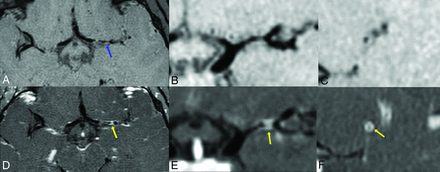

Vessel wall enhancement within the M1 left MCA. Vessel wall imaging targeted to the left middle cerebral artery with axial pre- (A) and postcontrast (D) 3D T1 volume isotropic turbo spin-echo acquisition sequences, with reformatted coronal images; B and E, respectively). Pre- (C) and postcontrast (F) reformatted sagittal images en face to the M1 left middle cerebral artery at the level of the blue and yellow arrows, respectively. There is wall thickening (blue arrow) and marked concentric contrast enhancement of the M1 left middle cerebral artery at the segment of stenosis (yellow arrows). The imaging findings, in conjunction with the clinical history, were consistent with FCA-inflammatory type.